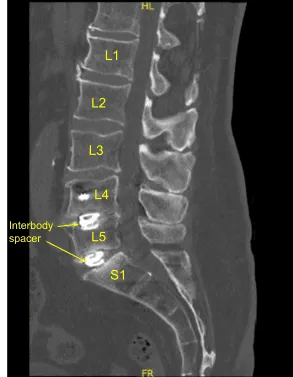

This patient previously underwent L4 to S1 minimally invasive transforaminal lumbar interbody fusion. They did well and recovered, however subsequently developed recurrence of their low back pain, had various injections and nonsurgical treatments including a sacroiliac joint fusion.

However, their back pain only worsened. Imaging showed loosening of bilateral pedicle screws and signs of pseudarthrosis. Surgery was recommended to stabilize the lumbar spine. The risks, benefits, alternatives and potential complications of the surgery were explained to them.

The patient was draped sterilely. CT scan was obtained, and data was transferred to the neuronavigation computer. Neuronavigation techniques were used to reposition and replace bilateral sacral screws which were upsized both in diameter and length until tight.